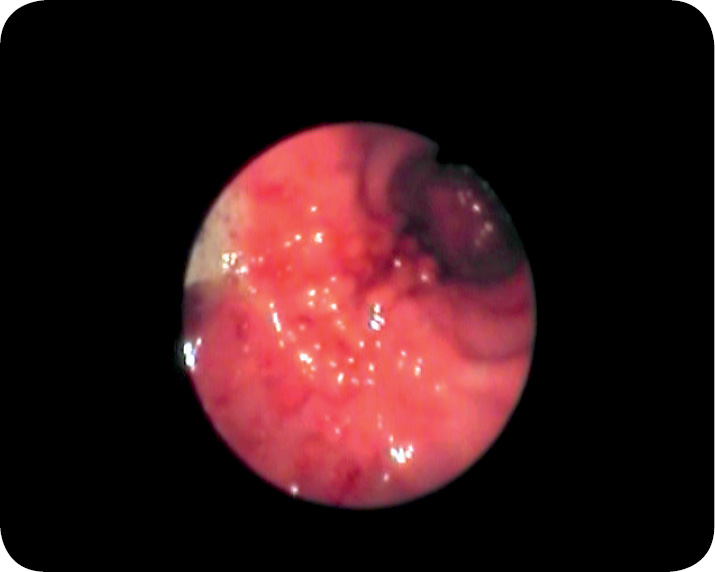

Podczas badania endoskopowego stwierdzono: błonę śluzową przełyku makroskopowo normotypową, zamknięty dolny zwieracz przełyku, obrzękniętą, zaczerwienioną, kruchą błonę śluzową trzonu i części odźwiernikowej żołądka z obecnymi nadżerkami i owrzodzeniami, utrudnione wprowadzenie endoskopu do części odźwiernikowej żołądka oraz brak możliwości obserwowania zwieracza odźwiernika, co było konsekwencją silnego zwężenia części odźwiernikowej żołądka (ryc. 1 i 2). Z części odźwiernikowej żołądka pobrano wycinki błony śluzowej do badania histopatologicznego.